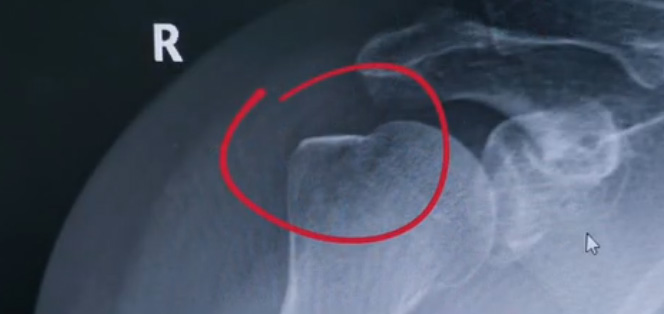

肩關節(jié)的X射線片子,看到沒有明顯的骨折,但是實際上已經骨折了。那么是如何發(fā)現(xiàn)的呢?醫(yī)生對于做出疾病診斷的時候,會選擇什么樣的檢查方式。也更好的配合醫(yī)生,來解決問題。1米高的地方摔了下來,右側肩關節(jié)與地面相撞受傷了。當時的胳膊還能活動,疼痛感很明顯,但是在家觀察了一天,這個腫脹沒有明顯的加重。然而問題是什么呢?疼痛始終不能緩解,所以就需要到醫(yī)院檢查。醫(yī)生查看關節(jié)的受限也很明顯,尤其做外展這個動作的時候,幾乎沒辦法自行完成。肩關節(jié)內的這個韌帶和肌腱可能還沒有發(fā)生嚴重的損傷。

首先做一個普通的X光檢查,看一看有沒有大的骨折或大的問題。結果是沒有發(fā)現(xiàn)太嚴重骨折損傷問題。結合病史,還是有點疑惑。因為疼的太厲害。x光檢查和他的疼痛之間不匹配,患者沒有骨頭的損傷,疼痛不至于達到這么嚴重的一個程度。是否有一種情況掩蓋住了病情。這也是X線檢查的通病。x光檢查它是一個二維的檢查,有可能患者肩關節(jié)啊發(fā)生了骨折。但是它的位置被前方或者側方的這個骨頭遮擋住了。不是立體的就沒辦法看到后方的情況。想要更加進一步的明確問題,判斷是否有骨頭的損害怎么辦?

進一步就是查CT,可以更全面的角度去判斷問題的所在。就會發(fā)現(xiàn)是否骨折可以看到確實存在著骨折,還好骨折不算嚴重。可以說是一個骨裂。這個肩關節(jié)與地面撞擊的時候,暴力沒有達到那么強。讓骨頭整個發(fā)生一個巨大的斷裂,而是造成了一個小的劈裂。適當?shù)倪M行一些抗炎止痛藥的使用。適當?shù)倪M行一些消腫治療,患者癥狀也就消失了。